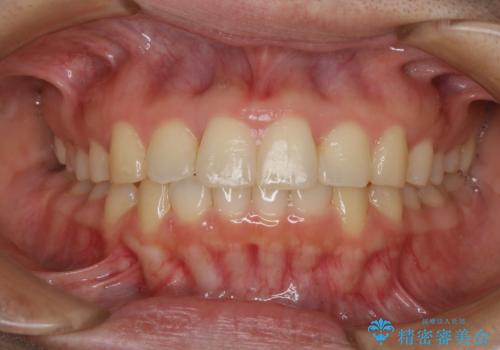

上下のデコボコを治したい インビザラインによる矯正治療